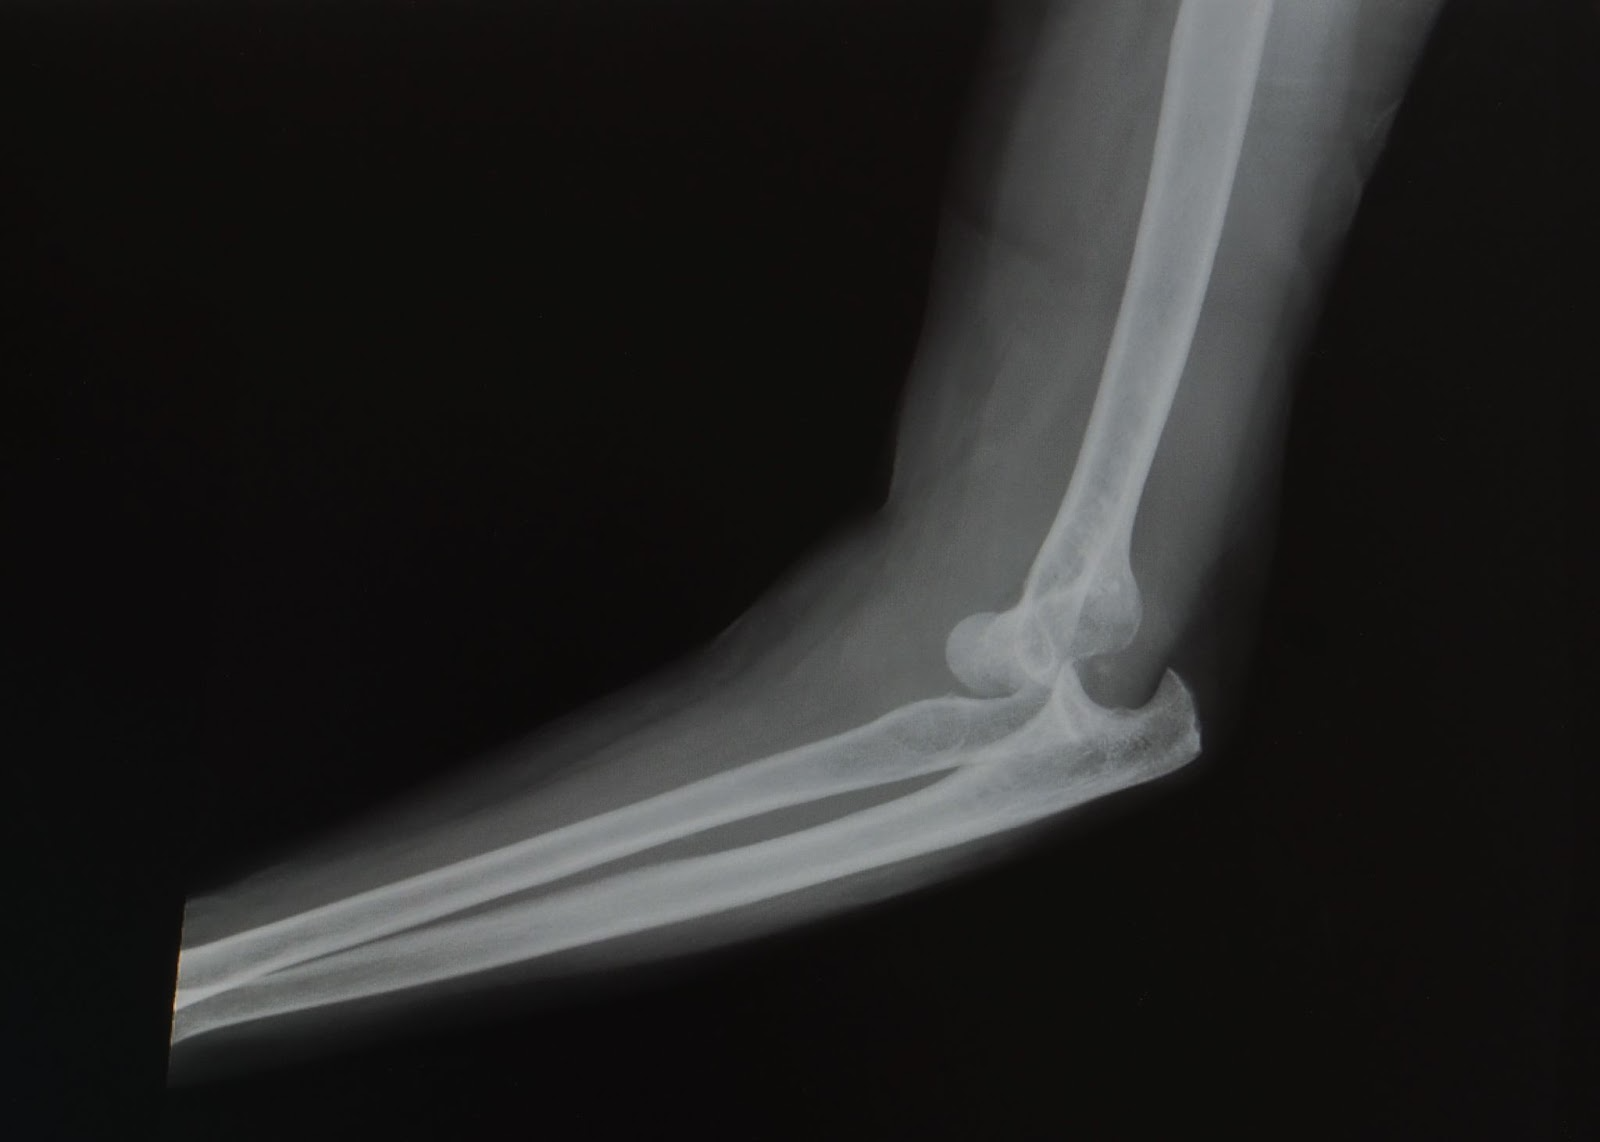

Posterior Elbow Dislocation, Oblique XRay, dislocated, Annotated. JETem 2016 JETem Forms Of Elbow Dislocation a dislocated elbow occurs when the elbow bones no longer connect. Elbow dislocations can be complete or partial, and. elbow dislocations are a common large joint dislocation experienced in children and adults. The radius and ulna articulate. elbow dislocations are common elbow injuries which can be characterized as simple or complex. simple dislocations of the elbow. Forms Of Elbow Dislocation.